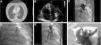

Once the diagnosis of PTE was confirmed, the indication of immediate perfusion due to its high risk was established and the patients were referred to the unit of hemodynamics to perform one PTT since the systemic fibrinolytic treatment was contraindicated. The percutaneous technique used was the same one in all the cases and consisted of obtaining right femoral venous access, make one pigtail catheter advance through both pulmonary arteries and inject contrast in order to identify the occluded branch. Once the branch to be treated was identified an interchange was tried from extra support guide-wire to catheter-guide-wire or 8F sheath (e.g., Torq Vue®, St Jude Medical) that was placed proximal to the thrombus. Fragmentation was accomplished using one pigtail catheter and introducing it through the 8F sheath; then aspiration was attempted through such sheath with support from multipurpose catheters (Fig. 1). During the PTT all patients received treatment with IV sodium heparin with one dose adjusted to activated coagulation time values of 200s, being the infusion continued when completing the proceeding adjusted to APPT-ratio values of 1.5–2. In all the cases, one variable amount of thrombus was extracted that would lead to significant clinical and hemodynamic improvement.

(A) CT-angiography of pulmonary arteries showing thrombotic content in the 2 main pulmonary arteries. (B) Transthoracic echocardiogram, apical four-chamber plane, severe dilation of right ventricle. (C) Basal left pulmonary angiography. (D) Fragmentation using pigtail catheter. (E) Left pulmonary angiography after mechanical thrombectomy. (F) Aspirated thrombotic content (arrows).

Before and after the proceeding, pulmonary pressures were measured invasively and an average reduction of the mean pulmonary pressure of 17.0±14.8mmHg was observed. In the patient with VA-ECMO support no measurements of the pulmonary pressure were taken since such measurements cannot be assessed with this kind of support. Improvement of the right ventricular function in the echocardiogram performed 72h after the proceeding was confirmed. The telediastolic diameters of the basal, medial, and longitudinal right ventricle were reduced an average of 16.5±3.8mm, 10.3±4.3mm, and 2.5±0.5mm, respectively. Also, the right ventricular function measured using the tricuspid annular plane systolic excursion (TAPSE) was increased an average of 10.3±4.4mm. After 6 months, the subjects from cases #1, #2 and #4 are still alive with no signs of developing pulmonary hypertension in the control echocardiogram.